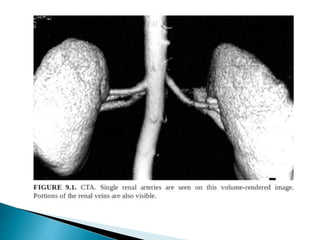

 CT is the preferred imaging due to better spatial resolution

and sensitivity to vascular calcifications and renal stones.

 CTA >> MRA

1. Distinguishing single/two main renal arteries.

2. Anatomy and to identify the point at which first branch

occurs.

3. Renal venous anatomy,

4. Tiny polar accessory arteries.